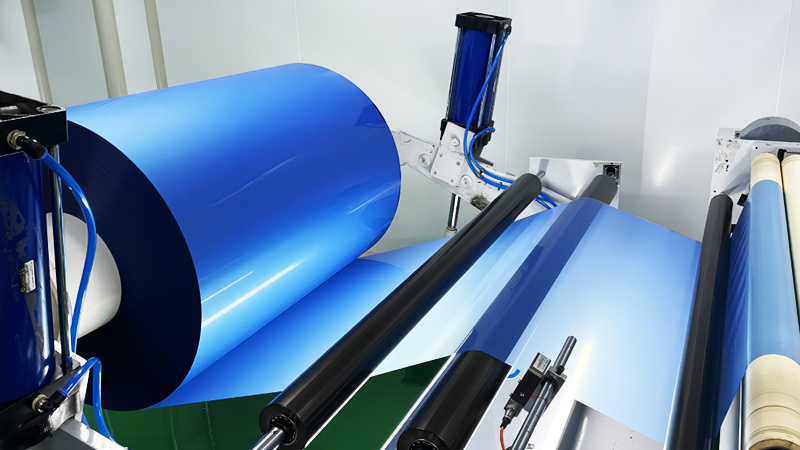

Independently develops and produces thermal film, medical laser film, and medical printing Film and other products.

Nanyang Qinghe Medical Technology Co., Ltd. was established in 2019. It is a technology-based enterprise engaged in the research and development, production and sales of medical films. The company has a factory area of 2,000 square meters, has independent intellectual property rights, has obtained 3 invention patents, 16 utility model patents, has a trademark registration certificate for the "Jiangying" brand, and independently develops and produces thermal film, medical laser film, and medical printing. Film and other products. The company's service personnel and technicians have been working for more than ten years and serve more than 600 medical customers and medical institutions in China. The products are exported to ten ASEAN countries, five Central Asian countries, South Asia, South America, Africa and other regions. The products and The service is widely praised, and there are many service cases from well-known foreign medical institutions.

The company has a factory area of 2,000 square meters, has independent intellectual property rights, has obtained 3 invention patents, 16 utility model patents.

Independently develops and produces thermal film, medical laser film, and medical printing Film and other products.